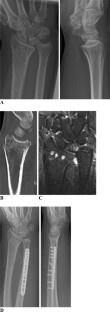

Fig. 2

Fig. 3

Fig. 4